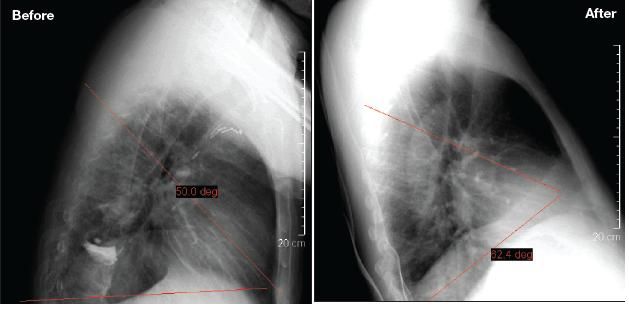

Chest wall deformities may cause restrictive ventilatory defect, often with a preserved residual volume and normal DLCO. The most common condition is kyphoscoliosis associated with acquired or congenital deformities. The severity of this condition is defined by measurement of the Cobb angle of curvature that is formed by the edges of the vertebral convex.

Our patient had a vertebral compression in the lower thoracic spine, which may have contributed to the ventilatory restriction. The lung volumes, however, started to improve before the vertebroplasty was performed. Furthermore, Cobb angle measurements on lateral chest radiographs before and after vertebroplasty were comparable (Figure 5). Hence, chest wall restriction does not entirely explain the reduced lung volume.

Figure 5 –These lateral chest radiographs were obtained before and after vertebroplasty. The red lines define the Cobb angles. The Cobb angle measurements before and after vertebroplasty were comparable, suggesting that chest wall restriction was not the cause of the patient's reduced lung volume.